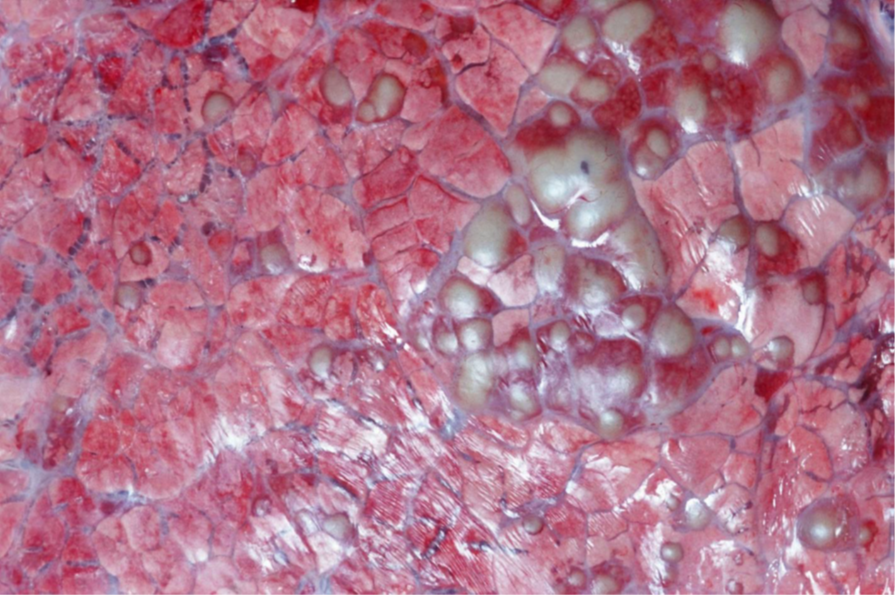

Rind, Leber: Hochgradige, diffuse Hepatolipidose

Leber

• Organ diffus verändert (A)

• Aufgehelltes Parenchym (hellbraun, gelbbraun, ocker….)

• Organ geschwollen (stumpfe Ränder, Kapsel steht unter Spannung → bei Einschnitt klaffen die Schnittränder auseinander und die Schnittflächen wölben sich vor)

• Teigige Konsistenz, Parenchym leicht eindrückbar („brüchig“)

• Fettiger Glanz der Schnittfläche (B)

• hochgradige, vermutlich panlobuläre Verfettung (C)

Hochgradige diffuse Hepatolipidose

(sog. „Fettleber“)

Hepatose (primär nicht entzündlich bedingte Stoffwechselstörung der Leber)

Pathogenese: Angebot an Fett übersteigt die Stoffwechselkapazitäten der Leber

→ Angriffspunkte der Störungen können sein: die Fettaufnahme, der Transport, verschiedene Stufen der

Verarbeitung in der Leber sowie die Ausschleusung aus der Leberzelle

Zugrundeliegende Hauptursachen:

• Alimentär/nutritiv: „Mastleber“, erhöhtes Nahrungsangebot führt zu einer vermehrten Fettspeicherung,

oftmals Begleiterscheinung einer allgemeinen Adipositas (nicht bei Sw und Pfd)

• Metabolisch: mit Hyperlipämie einhergehende Stoffwechselveränderungen → Hypoglykämie-Fettleber-

Syndrom der Zwerghunderassen, Hungerzustände (Hyperlipämiesyndrom der Ponys, Fettlebersyndrom der

Katze), Gestationshepatose bei Rd (nach Einsetzten der Laktation) und kl. Wdk (letztes Drittel der

Trächtigkeit), Diabetes mellitus beim Flfr.

• Hypoxisch: Anämie, Ischämie (z.B. durch Rückstau/verlangsamten Blutfluss im Rahmen einer

Rechtsherzinsuffizienz)

• Toxisch: z.B. Aflatoxine, Tetrachlormethan und Phosphor

DDx: Amyloidose